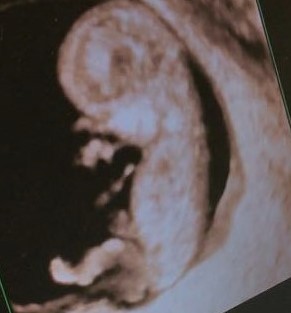

We had another scan today with our consultant to check everything is ok as I had quite a heavy bleed a couple of weeks ago. It stopped the day after and wasn’t fresh blood so I tried not to worry but it was great today to get the reassurance that everything is still ok. He/she has gone from a blob to a little baby in just 2 weeks. Booom! Mind blown!! I still have to pinch myself that this is all happening. 11 weeks! Not long before the 12week milestone now.